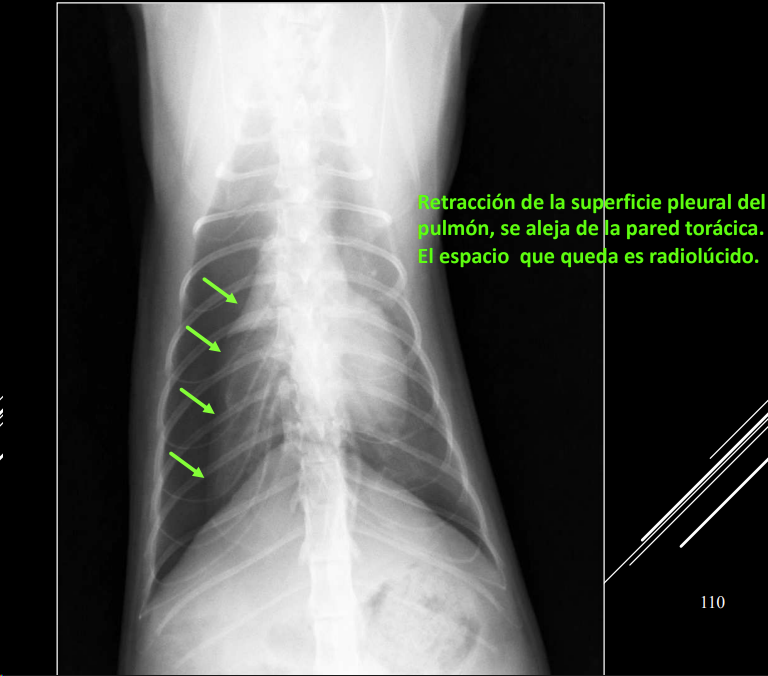

Neumotórax

Si hay un neumotorax y neuromediastino, el neumomediastino siempre es el causante

- Aire en cavidad pleural.

- RX:

- Desplazamiento dorsal del corazón (LL).

- Colapso pulmonar.

- Trama pulmonar no llega a pared torácica.

- Espacio radiolúcido entre pulmón y pared.

Cuando hay un neumotorax, al retraerse el pulmon se presentara un patron alveolar. Si el aire puede ir a ambos lados las presiones se compensan, anotensión. Si solo entra y no sale aumentara la presion y tendremos un neumotorax atensión